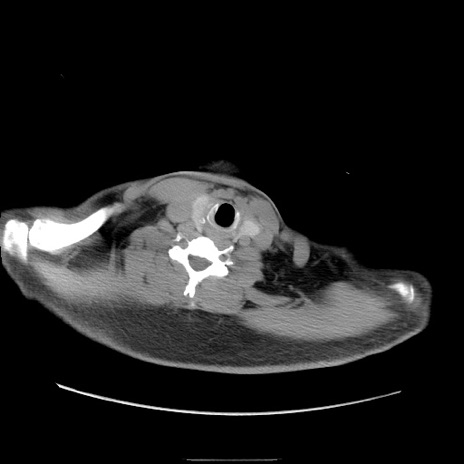

冠状断像

【症例】50歳代男性

【主訴】腹痛

【現病歴】AVMからの被殻出血のため回復期リハ病棟入院中。 本日午後3時頃急に下腹部痛が出現した。

【既往歴】AVM、被殻出血、虫垂炎、高血圧

【身体所見】意識晴明、左半身不全麻痺、会話の理解は良好、36.5°C、腹部:膨隆、全体に板状硬、下腹部正中に圧痛点あり、反跳痛-、筋性防御不明、右下腹部にope scar

【データ】WBC 9400、CRP 0.06